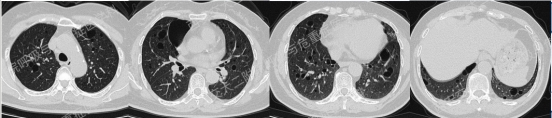

上图所示肺部囊性病变,双侧多发、大小不一,壁薄,形状不规则,呈圆形及扁平状为主,部分融合,分布多在纵隔胸膜下。入院后查血尿粪常规、肝肾功能电解质、凝血功能、血糖血脂心肌酶、BNP、肌钙蛋白正常;红细胞沉降率23mm/h,PCT、CRP正常;TB-spot阳性(阳性对照管反应水平123.49 pg/mL),TB-DNA、PPD试验、痰X-pert、痰涂片、痰培养均阴性;女性肿瘤标志物全套未见异常;结缔组织病相关指标:自身抗体ANA 1:100、CENP B阳性,CCP抗体25.1U/ml(正常参考值<17U/ml),ANCA、抗核抗体谱、体液免疫全套均阴性;血气分析大致正常,肺功能检查: FEV1占预计值78.2%,FEV1/FVC 69.55%,RV/TLC 49.62%,支气管舒张试验阴性,FeNO50 29.2ppb。

患者无吸烟史,二手烟接触不多。追问家族史,父母已故(具体不详),兄弟姐妹6人,大姐有肺大泡病史,未具体诊治,育有2子,均体健。进一步行双肾CT平扫提示双肾轻度积水,进一步行全外显子基因检测,回报FLCN突变:

该例患者BHD诊断明确,无皮肤及肾脏受累,仅表现为多发囊性肺病变。建议忌烟,避免受凉、劳累及剧烈运动,防范气胸。鉴于肺功异常,建议每年复查1次胸部CT及肺功能检查;每3年筛查1次肾脏MRI。同时建议其兄弟姐妹及其子完善症状前FLCN基因检测。